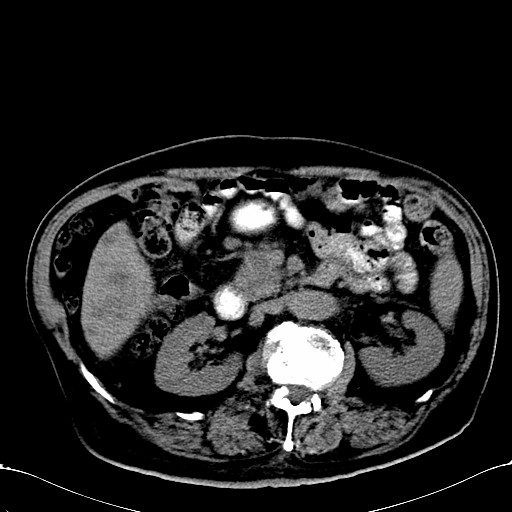

标题: CT28270:胰管扩张,肝多发占位 [打印本页]

标题: CT28270:胰管扩张,肝多发占位

患者,男,75岁。

肝脏多方低密度结节,边缘模糊,考虑多发转移,胰管明显扩张,建议增强扫描钩突情况

肝脏多发低密度灶,胰头似呈低密度,胰管扩张,建议增强,

胰管显著扩张,但胆总管未见扩张征象,不太符合胰头占位!考虑慢性胰腺炎.胃窦占位并肝内转移可能!mrcp胃镜增强一起上!